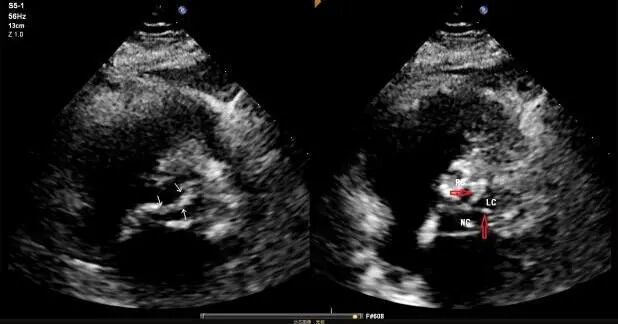

高龄患者,因“反复胸痛2年,加重伴气促1周”入院,超声心动图提示主动脉瓣极重度狭窄(图A),主动脉CT提示三叶式主动脉瓣,瓣叶增厚,重度钙化,L-R钙化高位粘连(图B),患者已有心源性休克、晕厥的表现,病情危重,更为棘手的是,患者同时存在反复消化道出血,经多学科会诊,明确诊断为海德综合征(Heyde综合征)——一种因主动脉瓣狭窄导致胃肠道血管发育不良继而引发出血的严重并发症。

B:主动脉根部CT分析:三叶式主动脉瓣,瓣叶增厚,重度钙化,L-R钙化高位粘连